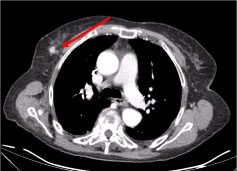

A full-body Computer Tomography (CT) revealed multiple necrotic cervical lymph nodes, the biggest in the left supraclavicular fossae and a nodule in the right mammary gland, irregular with hyperattenuating sign suggestive of vascularization (Figure 2 and Figure 3).

Figure 2: Neck CT scan: Multiple necrotic cervical lymph nodes, the biggest subcutaneous, 27 mm in diameter (arrow). View Figure 2

Figure 3: Chest CT scan: 10 mm lesion on the right mammary gland, nodular irregular, with a hyperattenuating sign suggestive of vascularization (arrow). View Figure 3